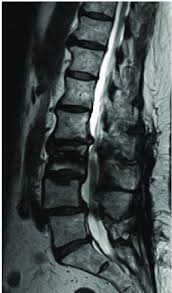

Disc Bulg L2-L3

L2-L3 Herniation: The L2 nerve root is responsible for the iliopsoas muscles. A disc herniation at this level may cause weakness in an iliopsoas muscle, which may cause difficulty while walking up the stairs and/or pain that radiates into the front of the thigh.